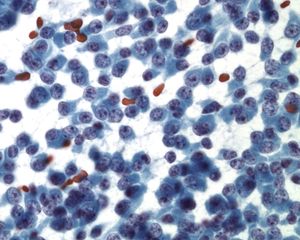

Neuroendocrine Tumor –MN07-R09706 and N13-6431

- Incidence: ~2-5% of pancreatic neoplasms; ~50% functional and 50% nonfunctional

- Age, Gender: Any age but most between 40-60 years; M=F

- Prognosis and Therapy: Small neoplasms without adverse prognostic features are curable by surgical resection; prognosis is related to tumor size, mitotic rate, necrosis, extrapancreatic invasion, vascular invasion, and nodal or distant metastases

- Radiological Features: Solid, well-circumscribed masses, usually small (<2cm), but may be large (>6cm); can be cystic

Key Cytological Features: Pancreatic Neuroendocrine Tumor

- Discohesive, single cell "solid-cellular "smear pattern

- Uniform, monotonous population of cells with plasmacytoid features

- Coarse, speckled, “salt and pepper” chromatin pattern

- Nucleoli may be prominent

- Dense, finely granular cytoplasm